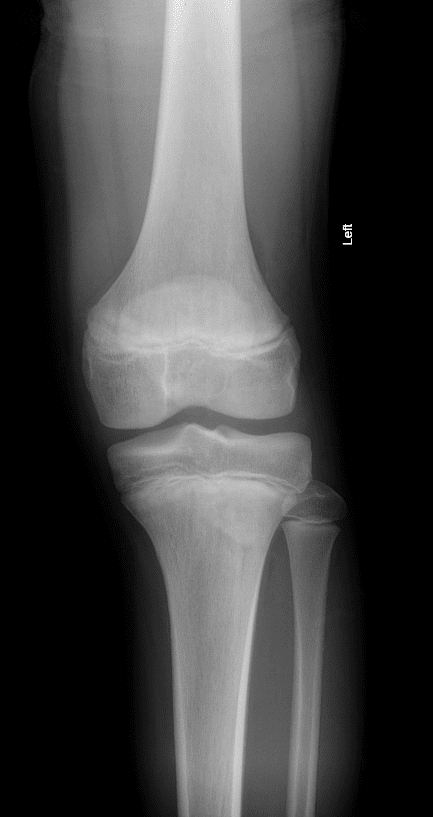

Viêm lồi củ trước xương chày

» Thông tin: Nam giới – 10 tuổi.

» Lâm sàng: Sưng đau đầu trên xương chày.